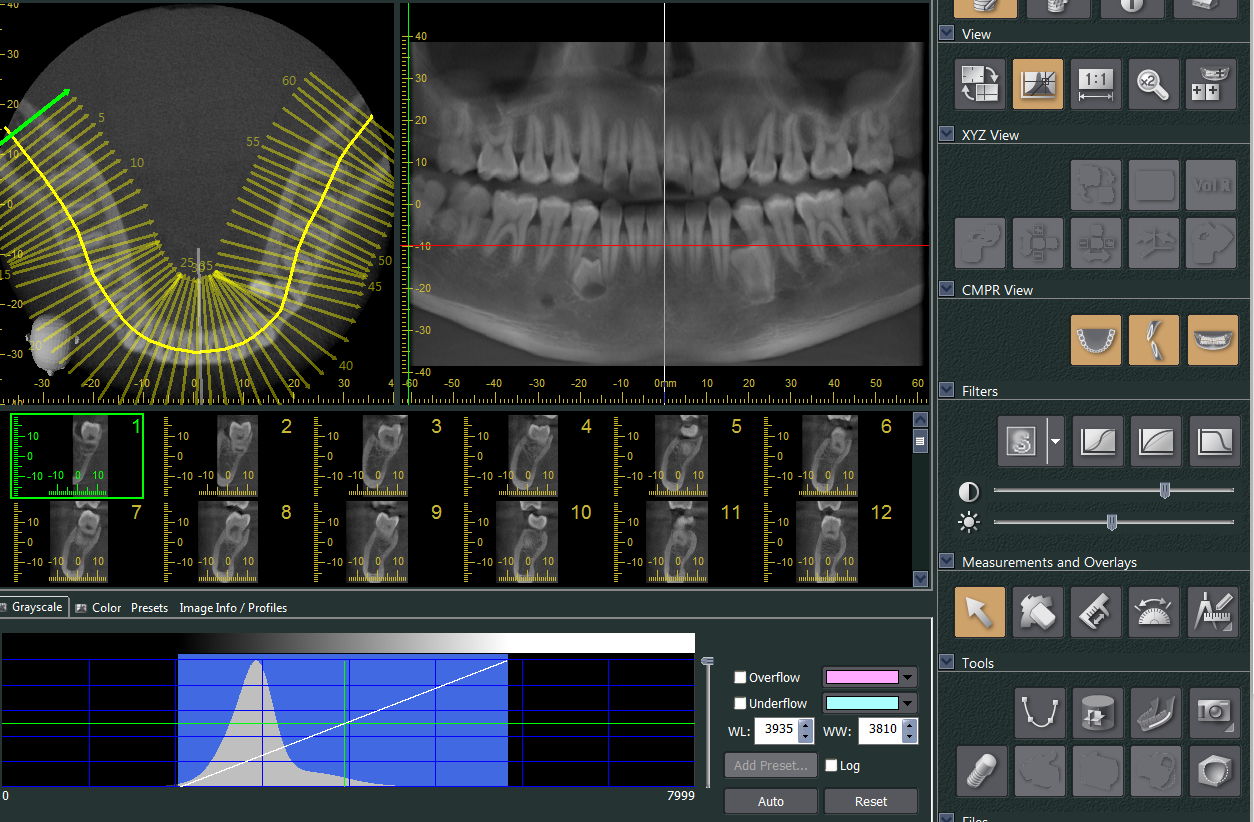

Tomografía Cone Beam 3D

La Tomografía Computarizada Cone Beam (TCCB) es una tecnología en rápido desarrollo que proporciona imágenes de alta resolución espacial del complejo craneofacial en tres dimensiones (3D). Durante la última década, el número de publicaciones relacionadas a la TCCB en la literatura se ha incrementado de manera significativa, pero la cuestión fundamental es si esta tecnología conduce a mejores resultados.